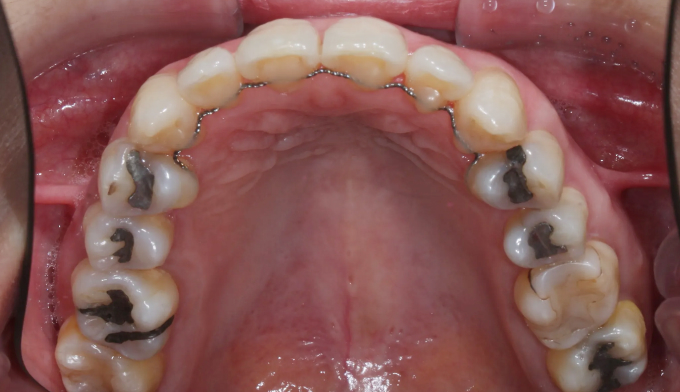

덧니

교정치료에 나이 제한은 없습니다.

건강한 잇몸을 가지고 있다면 60,70대에도 전혀 문제없고, 잇몸이 건강하지 못하다면 20대여도 교정이 힘들 수 있습니다.

아무래도 나이가 있으면 세포활성이 떨어지고 피부의 탄력도 줄어들기 마련입니다.

따라서 섣불리 발치교정을 진행하여서는 안됩니다. 오히려 교정후에 더 나이들어 보이는 경우가 생길 수 있기 때문입니다.

비발치교정을 통하여 치아를 배열하고 일부러 앞니를 조금 더 앞으로 이동시켜 깊어진 팔자주름을 옅게 만들어주었습니다.